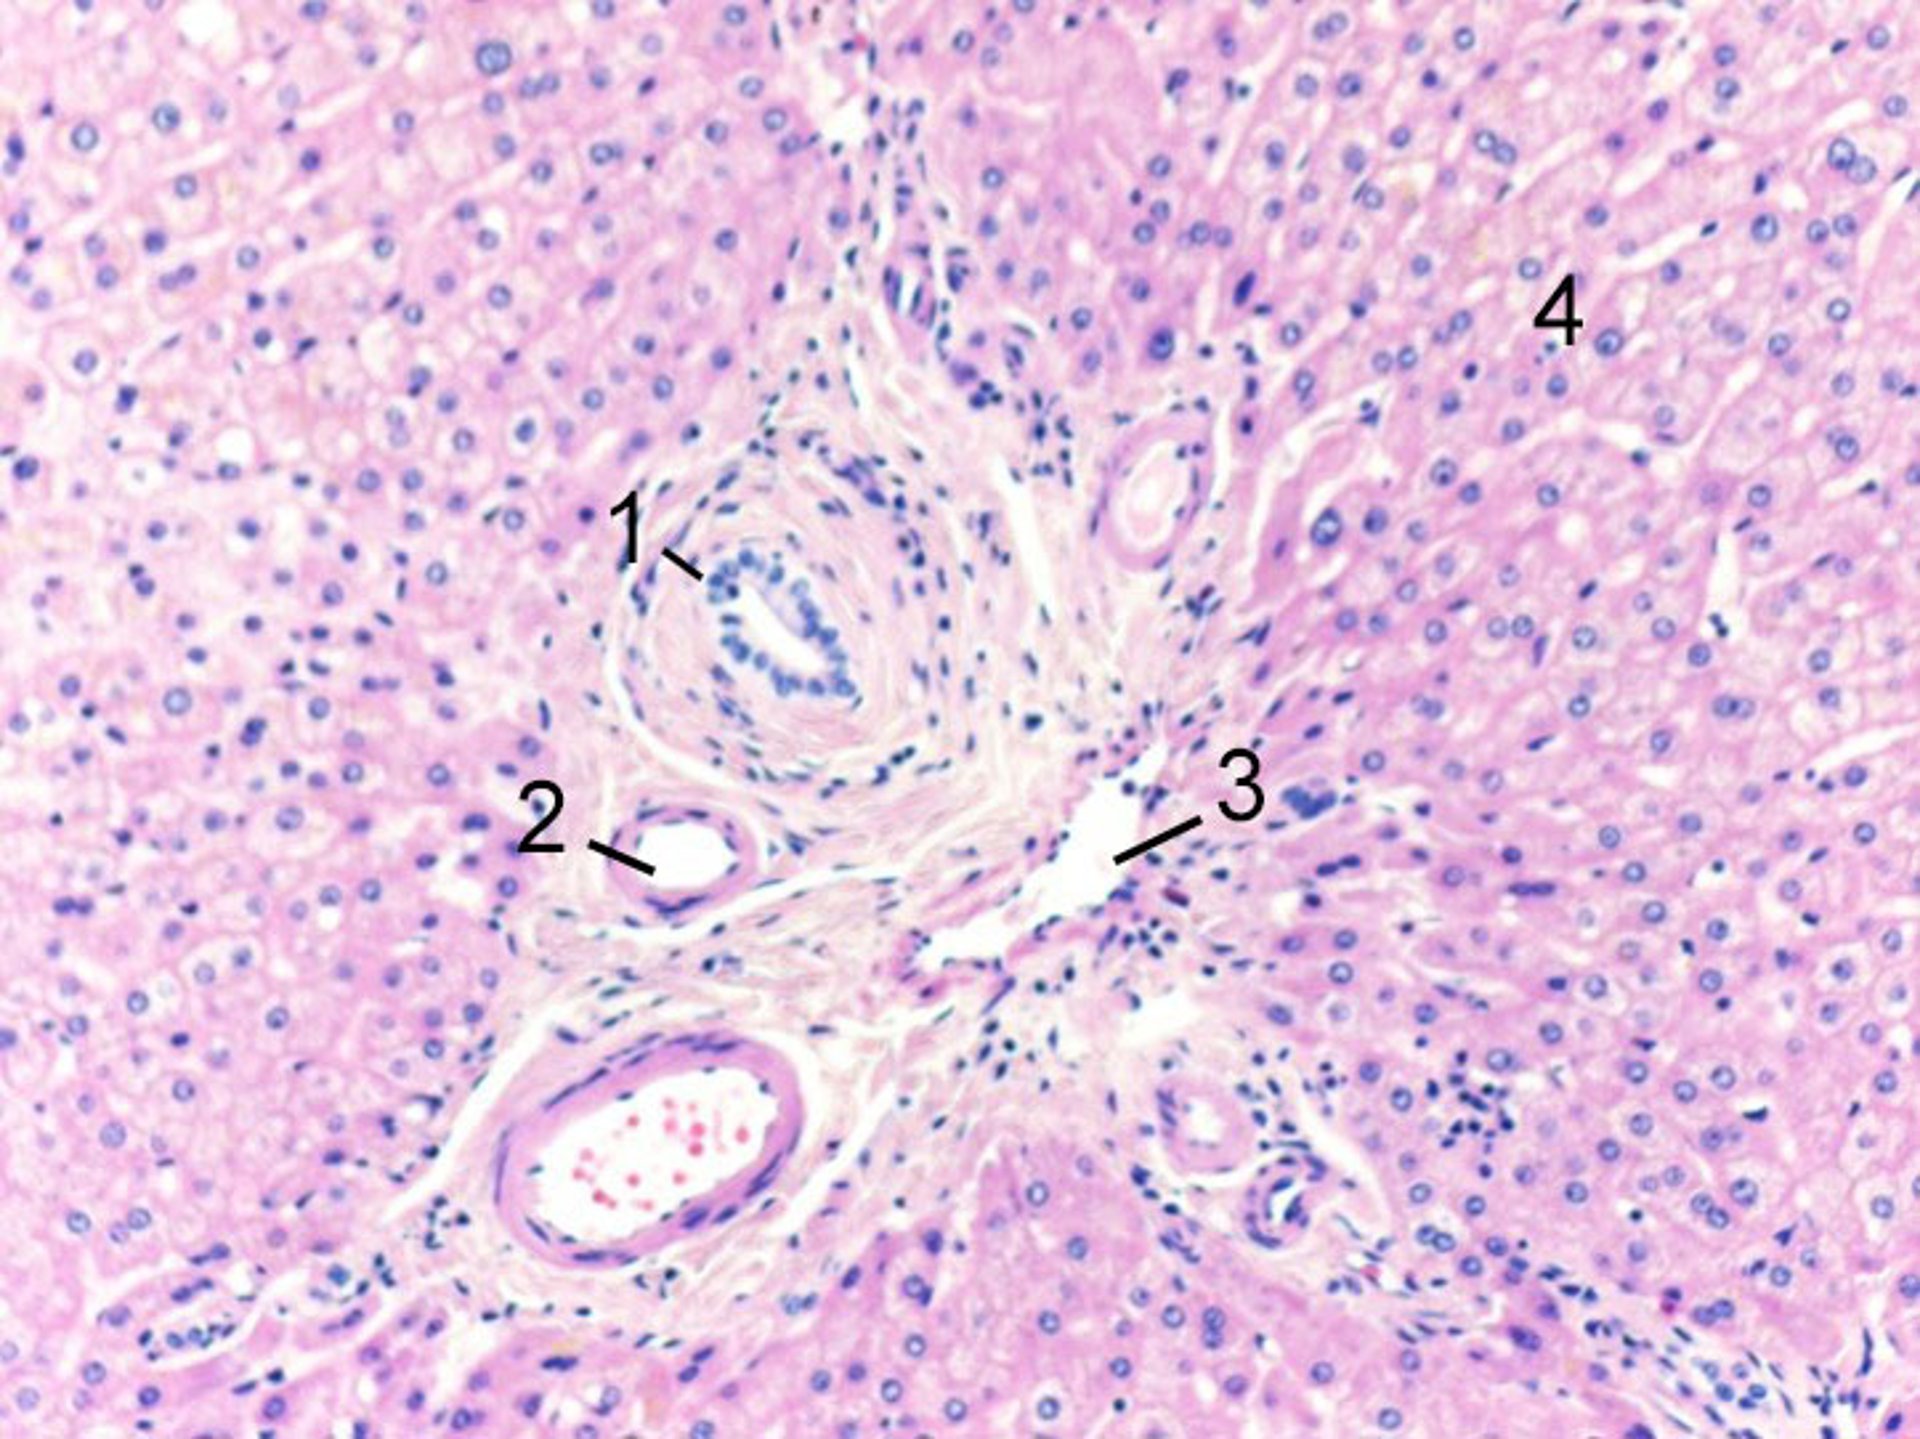

Tríada portal normal

1 = Rama del conducto biliar; 2 = rama de la arteria hepática; 3 = rama de la vena porta; 4 = hepatocitos.